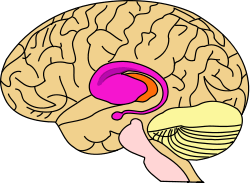

purple=caudate and putamen, orange=thalamus | |

The striatum, also known as the neostriatum or striate nucleus, is a subcortical part of the forebrain and a critical component of the reward system. It receives glutamatergic and dopaminergic inputs from different sources and serves as the primary input to the rest of the basal ganglia system. In all primates, the dorsal striatum is divided by a white matter tract called the internal capsule into two sectors called the caudate nucleus and the putamen.[4] The ventral striatum is composed of the nucleus accumbens and olfactory tubercle in primates.[4] Functionally, the striatum coordinates multiple aspects of cognition, including motor and action planning, decision-making, motivation, reinforcement, and reward perception.[2][3][4]

The corpus striatum, a macrostructure which contains the striatum, is composed of the entire striatum and the globus pallidus.[5] The lenticular nucleus refers to the putamen together with the globus pallidus.[6]

The striatum is divided into ventral and dorsal subregions, based upon function and connectivity. The ventral striatum is composed of the nucleus accumbens and olfactory tubercle, whereas the dorsal striatum is composed of the caudate nucleus and putamen.